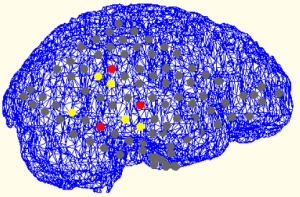

Project Summary: Epilepsy is one of the most  common diseases related to the disfunctioning of the central nervous system. For the patients whose drug therapy turns out to be ineffective, it is a common method to identify the locations of sources that trigger the seizure in the brain tissue and resect them through surgical means for treatment. When the surgical therapy is to be applied, seizure history, physical and neurological inspections, radiological imaging data (MRI, CT, PET), neuropsychological tests, psychiatric inspections and long term video and EEG monitoring data are evaluated by an expert group of neurosurgeons and neurologists. It requires to locate the epileptic focus using the EEG data recorded from the surface as well as from the deep sites located in the brain in order to improve the  widely  accepted current surgical planning approach. It is critically important to identify the  source locations of seizure activity for the epileptic surgery. This undoubtedly provides  a very important information to the clinical team for the surgical planning. The major aim of this study is to perform source localization using the surface and deep electrode EEG data obtained from epileptic patients and hence, to provide a biomedical support to the surgical planning. As a result, by applying a smaller number of electrodes it is aimed to offer less inconvenience to the patient as well as to reduce significantly the cost and duration of the surgical procedure.

Keywords: EEG source localization, epilepsy, deep/subdural electrode